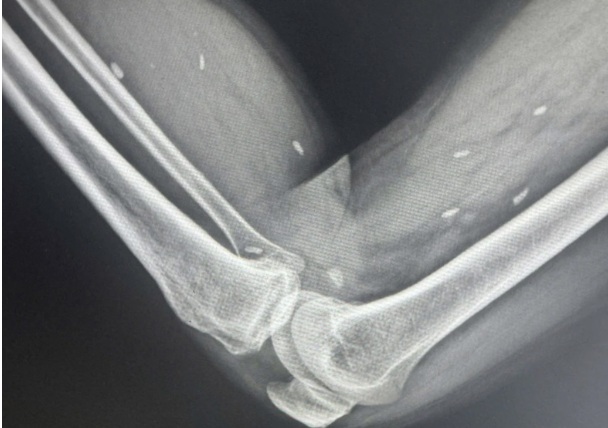

Kết quả cho thấy nhiều kén sán có kích thước tương đương hạt gạo, nằm rải rác trong các mô mềm vùng xương đùi và cẳng chân. Bác sĩ nhận định đây là hình ảnh điển hình của tình trạng nhiễm kén sán.

Hình ảnh trên phim X-quang. Ảnh: BVCC.